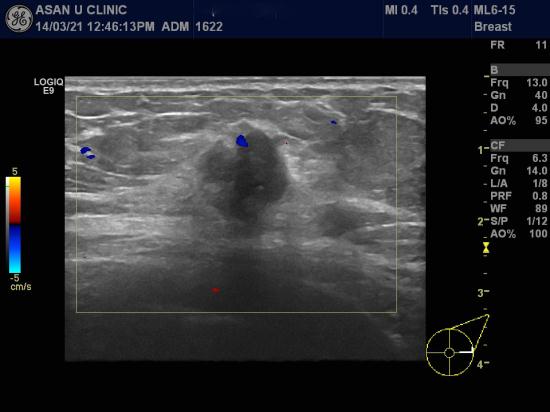

아산유외과 개원 후 80번째 유방암진단.

건강검진상 이상소견으로 내원한 57세 여성분입니다.

1.3 cm의 좌측 유방결절을 중심핵생검으로 침윤성 유관암 진단했습니다.

집안내력도 없고 나이도 많아 섬유선종일 줄 알았다며 놀라시는 모습입니다.

젊은 여성과 달리 폐경후 여성에서 섬유선종은 흔하지 않습니다.

꼭 확인해 보세요.